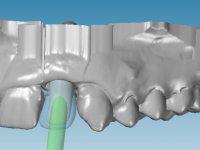

An impression was made on the implant with open tray technique using soft and regular consistency putty. At the laboratory, after confection of the work model, a diagnostic waxing was performed, which sought to find an aesthetic compromise solution. In this sense, a temporary workpiece screwed onto the implant was used to simulate the difficulties we would have with screwing the definitive work. This study abutment consisted of wax to reproduce soft and hard tissues, seeking to anticipate the use of ceramics of gingival and coronary shade. Also, part of the interproximal papillae corresponding to the distal portion of the 2.1 tooth and the mesial tooth of the tooth 2.3 were also waxed, anticipating the use of composite resin “chips” with gingival tonality. Finally, a veneer was waxed to correct the microdontia of the tooth 1.2. In this waxing, the vestibular emergence of the orifice for access to the screw of the implant abutment was evident. Once this therapeutic option was accepted, the implant abutment in polymerized composite resin was prepared at the lab, as well as the papillary "chips", also in composite resin of gingival tonality. Tested in the mouth, the abutment was screwed and the "chips" bonded. The access hole of the screw was filled with composite resin. In subsequent consultation, a gingivectomy was performed on the cervical contour of teeth 1.3, 1.2 and 1.1 with the aim of correcting the asymmetry between the first and second quadrant. After the soft tissues were cicatrized, a dental bleaching was performed according to the patient’s aesthetic requirements. Final impression on the implant was made using the silicone open tray technique, taking care to individualize the transfer piece by copying the emergence profile of the patient’s provisional abutment. At the laboratory, the impression yielded a definitive working model, on which the abutment was waxed on a plastic insert. This process was carried out with the orientation of a wall of silicone based on diagnostic waxing. The wax made on the plastic part was placed in a special holder that allowed its scanning in a laboratory scanner. This scan by CAD process informed the design of an abutment in Zr. later materialized by a CAM process. The Zr. abutment was tested in the mouth, validating its clinical and imaging establishment. During this consultation, the choice of color was made by the ceramist, of both the coronary ceramics and the ceramic of gingival tonality to be used. Individualized color scales were used. At the laboratory, the coronary and gingival ceramics were placed on the implant abutment and later, on a working model with refractory gypsum, a veneer of feldspathic ceramic was made. This veneer was built on a surface specially designed for this purpose in the abutment. This surface tried to reproduce a dental preparation performed for the same effect. In the mouth the abutment was screwed with a torque of 35N, the access hole to the screw was filled with Teflon and later filled with composite resin. The veneer was bonded onto the implant abutment using the conventional bonding technique, with relative insulation. For economic reasons, the patient did not proceed to perform the veneer on tooth 1.2. Although a limited aesthetic compromise was expected from the outset, a result was achieved which satisfied the patient.